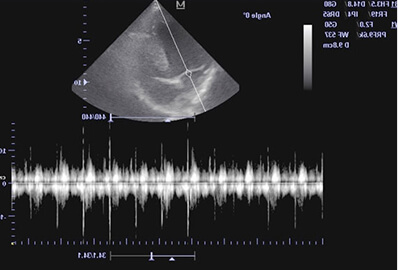

УЗИ брюшной полости кошки проводится с использованием ультразвукового сканера, который передает отражение звуковых волн, получая изображение в реальном времени. Перед диагностикой ветеринар наносит специальный гель на кожу в области живота. Затем плавно передвигает датчик по коже, чтобы получить изображение внутренних органов и структур.